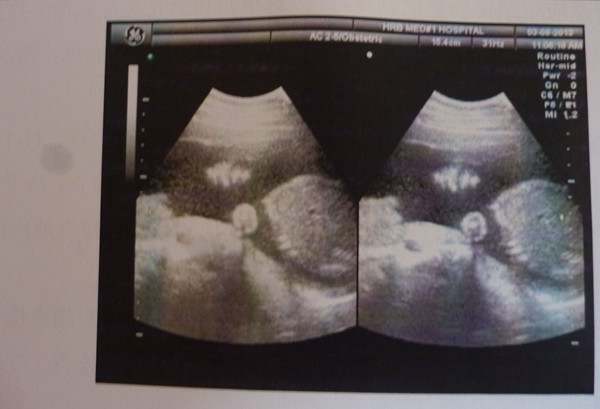

在怀孕的过程中,是不能避免B超的检查的,并且一段时间就要到医院检查一次,保证宝宝的安全,其中有一个能够看的更全面的,就是三维彩超,那么,我们现在就一起来看看孕妇三维最迟什么时候做?

妊娠11周到14周应该做彩超检查NT,20周到24周做三维或四维彩超排除大的畸形,其他时候做普通彩超就可以,比如查查胎儿发育情况,胎盘情况,羊水情况,不用都做三维四维的。

如果太早做排畸彩超,会因胎儿发育太小,一些组织还看不太清楚,无法达到清晰的观察胎宝宝的生长情况、筛查畸形的目的。做三维彩超也是分时间段的,最佳时间一般在女性怀孕的18-24周之间,因为这个时期胎儿基本在正常的发育过程中,怀孕3~4个月时,可诊断出无脑儿、胸腹部、四肢缺损等。

做三维彩超检查的时候,大家不用可以空腹检查,空腹检查反而会给大家的身体带来一些不便,出现低血糖的情况。在做检查之前,大家可以吃过早饭再去,这些对彩超检查结果并没有太大的影响。

做三维没有什么特别注意的产前也不需要憋尿之类的,但是进行手术前饮食不要太辛辣,不要受凉,防止影响彩超结果,多吃一些蛋白质高的食物,多喝水,保持一个良好的心情,有任何的不适做完彩超要及时的和医生交流,多多听取医生的建议。